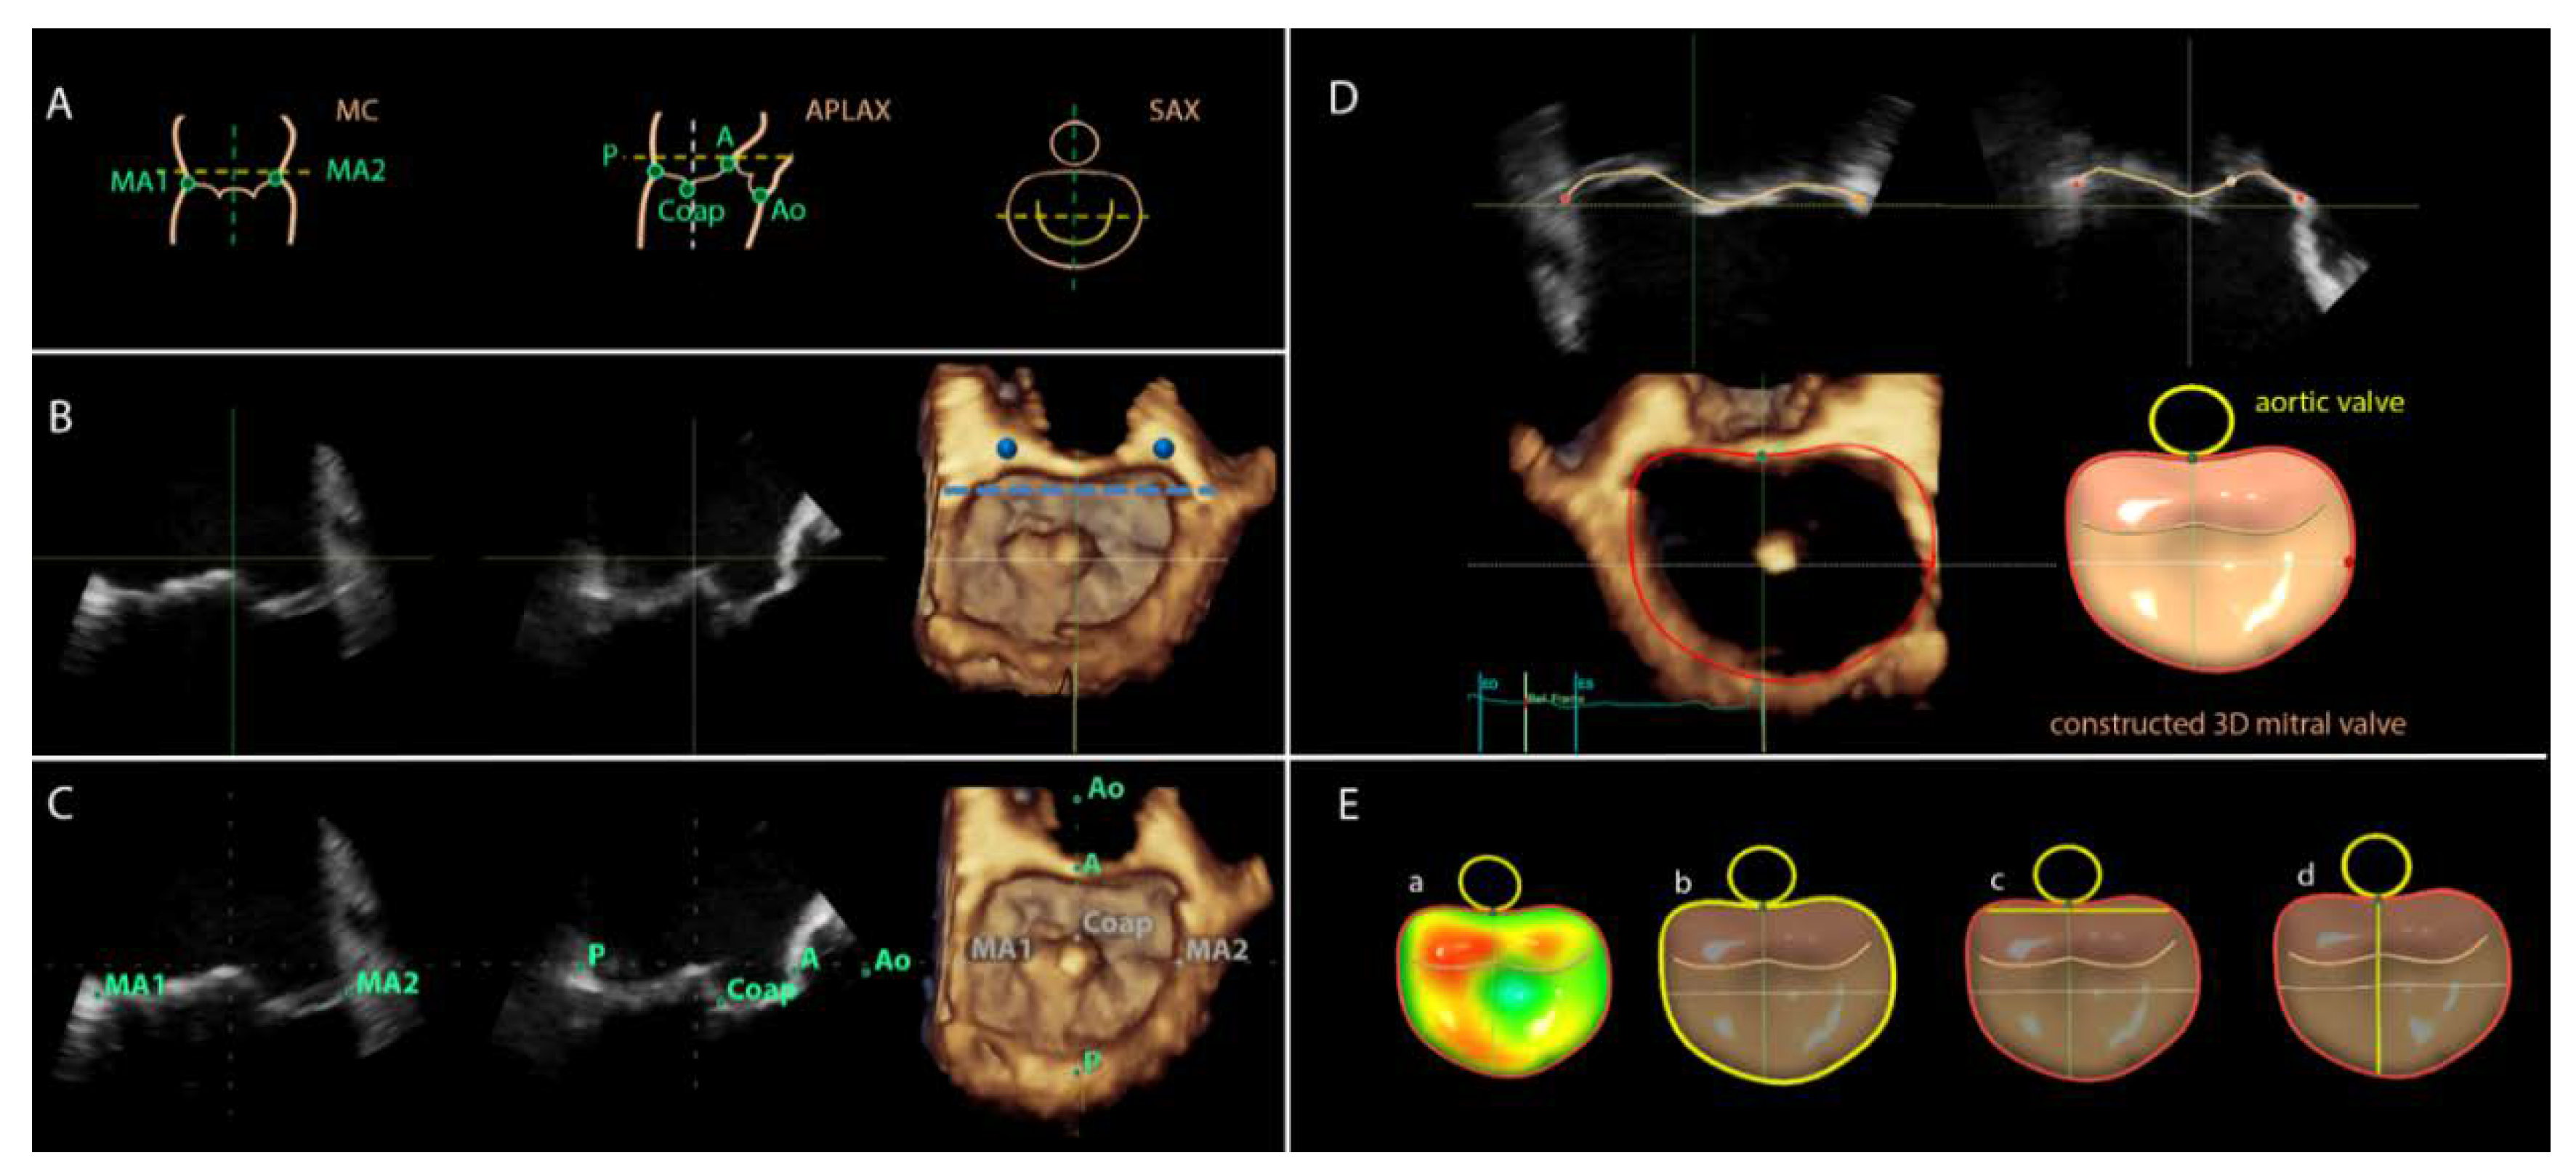

For image analyses the 3DTEE datasets were exported to an offline workstation (EchoPAC version 112.0.1; GE Vingmed Ultrasound AS) and were postprocessed with novel semi-automated software (4D Auto MVQ, GE Healthcare, Horten, Norway). From the 3D full volume dataset of the mitral valve, the mid-systolic frame was selected and the multiplanar reformation planes were aligned across the mitral commissures and perpendicular to obtain the mid-esophageal commissural (MC) and the apical longitudinal-axis (APLAX) views (Figure 1B). A third plane orthogonal to the MC and APLAX planes was oriented parallel to the lateral and medial trigones (Figure 1B). Subsequently, the landmarks were placed on the anterior, posterior, anterolateral and posteromedial points of the mitral annulus, the coaptation leaflet point and the aortic valve (Figure 1C). The software semi-automatically defined the perimeter of the mitral annulus and the area of the leaflets in the mid-systolic frame. The contours can be manually adjusted if needed. Thereafter, the software tracked the landmarks in all frames along the cardiac cycle to create a dynamic 3D mitral model. The contour tracking can be manually adjusted if needed on the reconstructed orthogonal planes (Figure 1D). After final approval of the reconstructed model, the software provided automated measurements of the D-shaped mitral annulus at mid-systole: annulus area (cm2) and perimeter (circumference, cm), intertrigonal distance (TT, cm), and septal-to-lateral (SL, cm) distance (Figure 1E).

Figure 1. Overview of work flow of the 3D transesophageal echocardiographic semi-automated software of 4D Auto MVQ. (A) Graphical illustration of alignment and landmark placing. (B) Using the multiplanar reformation planes, the guidelines are aligned parallel to the 2D mitral annulus hinges in the mitral commissural view (MC) and the apical long axis view (APLAX). In the short axis view (SAX), the mitral annulus is shown in 3D. The trigones (marked in blue) are identified by moving the horizontal guideline until it intersects at the aorto–mitral border. (C) Landmarks are placed in MC and APLAX with direct 3D visualization in SAX for review: A, anterior annulus; Ao, aortic valve; Coap, leaflet coaptation; P, posterior annulus; MA1, anterolateral mitral annulus; MA2, posteromedial mitral annulus. (D) The software automatically defines the perimeter of the mitral annulus. The contours are shown for review and for manual adjustment if needed. (E) The software provides annulus dimensions of the D-shaped annulus, which is displayed in a reconstructed 3D model. Highlighted in multicolor: a, area. Highlighted in yellow: b, circumference (perimeter); c, intertrigonal distance; d, septal–lateral distance.